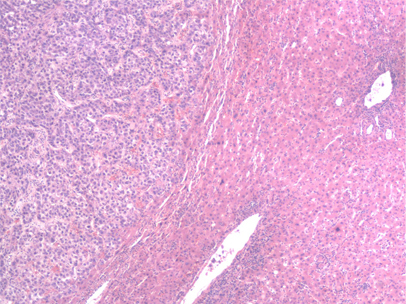

liver biopsy

Test

Most of the time, the diagnosis of HCC can be made radiologically in patients with cirrhosis without the need for liver biopsy. However, biopsy should be considered if the lesion remains indeterminate and in order to establish diagnosis of HCC in patients without cirrhosis or chronic hepatitis B virus infection.[7]

An ultrasound-guided percutaneous liver biopsy is favoured.

Core needle biopsy may be considered in certain clinical scenarios.[2]

Biopsy of liver lesions may also be necessary if clinical features suggest the possibility of metastatic liver disease or cholangiocarcinoma.

[Figure caption and citation for the preceding image starts]: Medium power microscopic view of a haematoxylin and eosin stained section depicting normal liver on the right and HCC on the left. A sharp boundary separates the distinct zones of normal liver and tumourFrom the personal collection of Badar Muneer MD, Florida Hospital Transplant Center, Orlando, FL; used with permission [Citation ends].